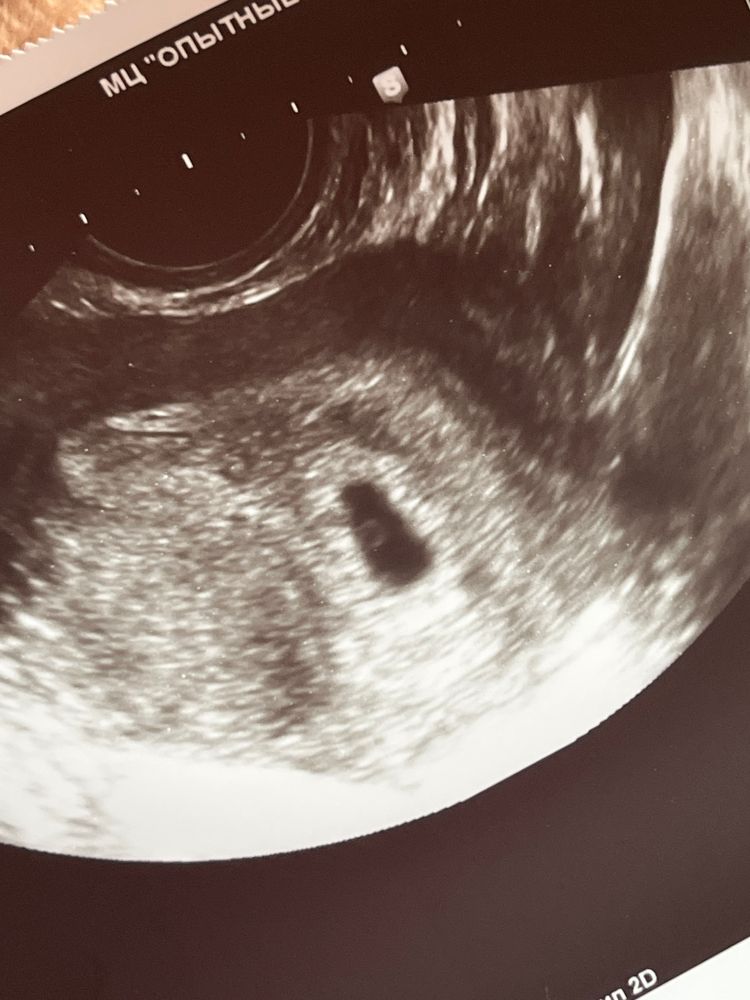

Первое узи

Лимоночка, желточный мешочек 3 мм,ПЯ 11

Мама индахаус, а это не может быть пустым плодным яйцом? Изображение

Евгения, желточный мешочек есть,это уже хорошо,рано просто для эмбриона